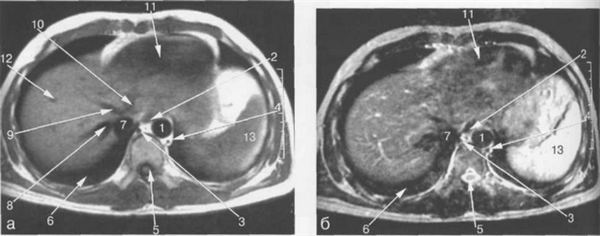

Рис. 11.9. МРТ брюшной полости в аксиальной плоскости на уровне печеночных вен.

1 — аорта; 2 — пищевод; 3 — непарная вена; 4 — полунепарная вена; 5 — спинной мозг; 6 — нижняя доля правого легкого; 7 — нижняя полая вена; 8 — правая печеночная вена; 9 — средняя печеночная вена; 10 — левая печеночная вена; 11 — левый желудочек сердца; 12 — ветви правой воротной вены; 13 — селезенка.

Рис. 11.10. МРТ брюшной полости в аксиальной плоскости на уровне пищеводно-желудочного перехода.

а-Т1-ВИ;б-Т2-ВИ.

1 — аорта; 2 — пищеводно-желудочный переход; 3 — непарная вена; 4 — полунепарная вена; 5 — ножка диафрагмы; 6 — нижняя доля правого легкого; 7 — нижняя полая вена; 8 — правая печеночная вена; 9 -средняя печеночная вена; 10 — желудок; 11 — селезенка.

Рис. 11.11. МРТ брюшной полости в аксиальной плоскости на уровне печеночных вен.

1 — аорта; 2 — желудок; 3 — хвостатая доля печени; 4 — левая ветвь воротной вены; 5 — передние сегменты правой доли печени; 6 — задние сегменты правой доли печени; 7 — нижняя полая вена; 8 — правая печеночная вена; 9 — правая ветвь воротной вены; 10 — левая доля печени; 11 — селезенка; 12 — диафрагма.

Правая печеночная вена расположена в правой межсегментарной борозде, которая отделяет друг от друга передние и задние сегменты правой доли печени (рис. 11.12, 11.13). Левая печеночная вена располагается в левой межсегментарной борозде и разделяет внутренний и наружный сегменты левой доли печени (см. рис. 11.9). Серповидная связка также может использоваться в качестве ориентира, разделяющего внутренний и наружный сегменты левой доли печени.